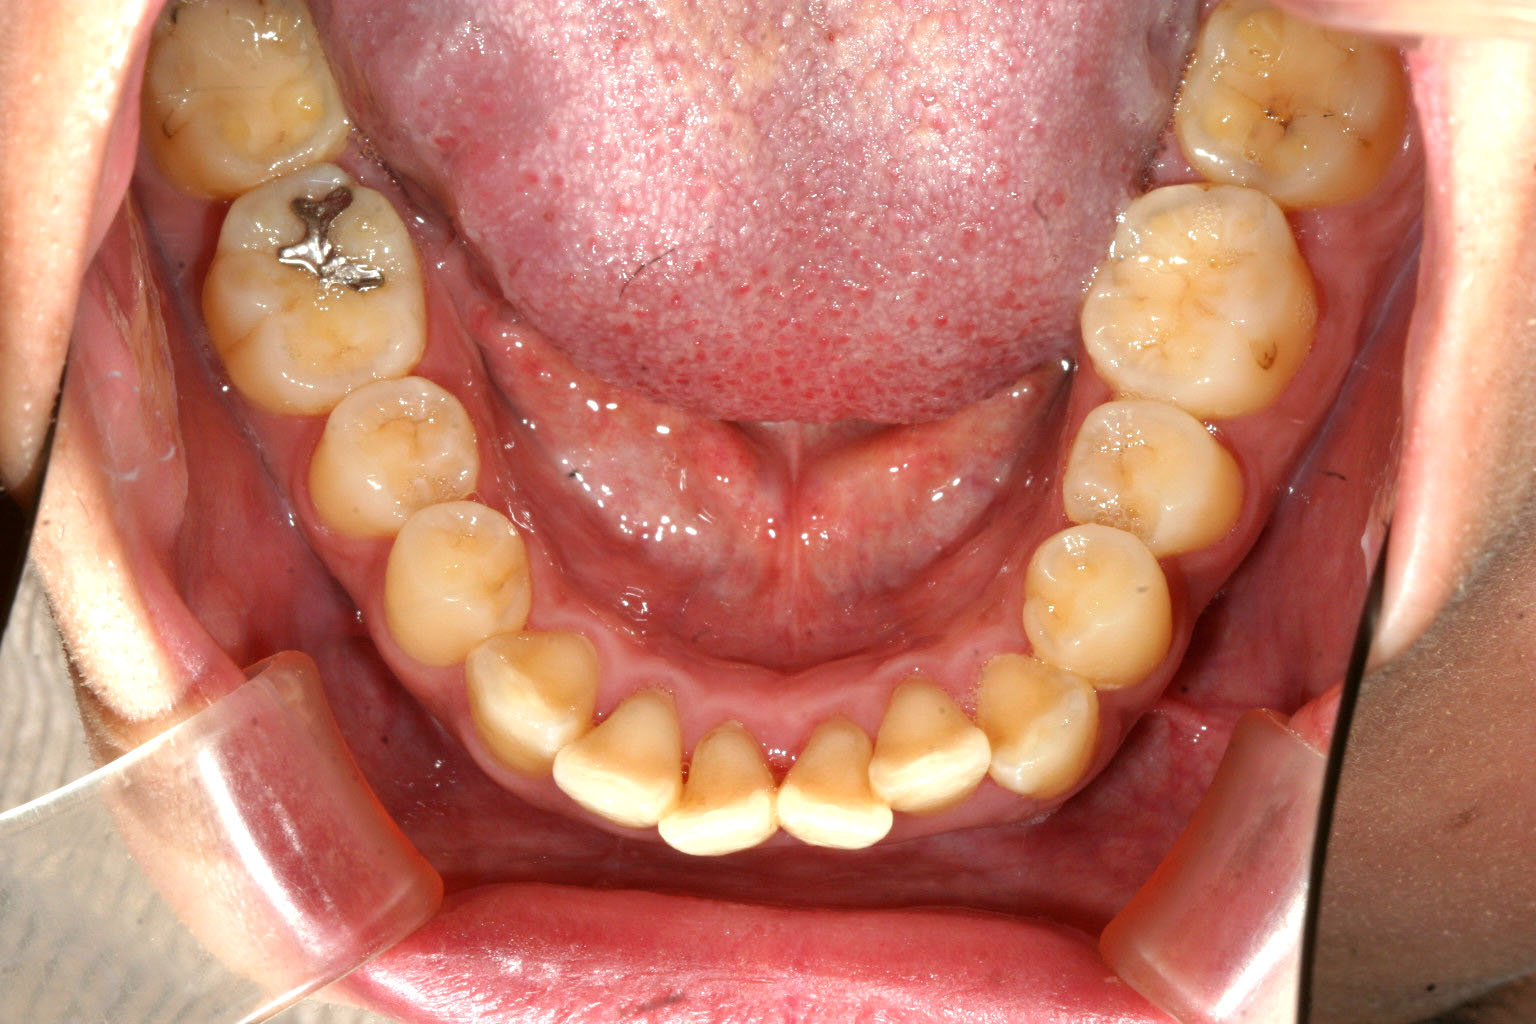

下顎にも少し叢生が見られます。

今回は非抜歯でと希望の為何処まで入るかやってみました。